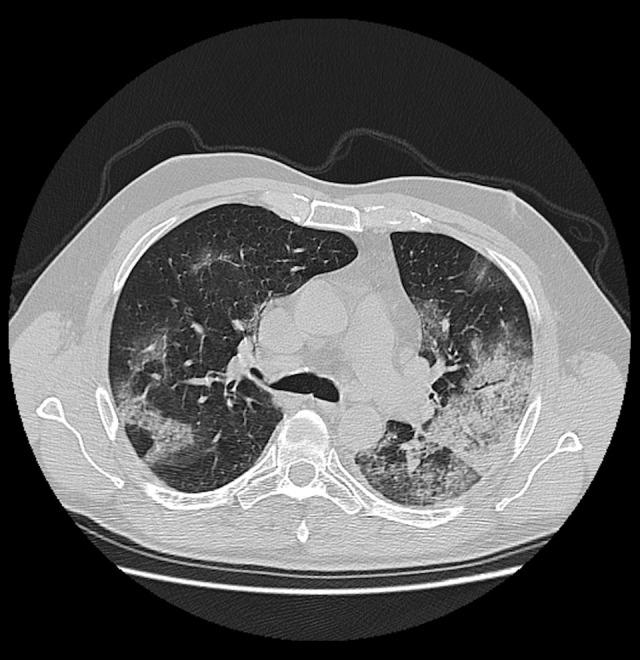

BACKGROUND Chest imaging may be taken into consideration in detecting viral lung infections, especially if there are no tests available or there is a need for a prompt diagnosis. Imaging modalities enable evaluation of the character and extent of pulmonary lesions and monitoring of the disease course. The aim of this study was to verify the prognostic value of chest CT in COVID-19 patients. MATERIAL AND METHODS We conducted a retrospective review of clinical data and CT scans of 156 patients with SARS-CoV-2 infection confirmed by real-time reverse-transcription polymerase-chain-reaction (rRT-PCR) assay hospitalized in the Central Clinical Hospital of the Ministry of the Interior in Warsaw and in the Medical Centre in Łańcut, Poland. The total severity score (TSS) was used to quantify the extent of lung opacification in CT scans. RESULTS The dominant pattern in discharged patients was ground-glass opacities, whereas in the non-survivors, the dominant pulmonary changes were consolidations. The non-survivors were more likely to have pleural effusion, pleural thickening, lymphadenopathy, air bronchogram, and bronchiolectasis. There were no statistically significant differences among the 3 analyzed groups (non-survivors, discharged patients, and patients who underwent prolonged hospitalization) in the presence of fibrotic lesions, segmental or subsegmental pulmonary vessel enlargement, subpleural lines, air bubble sign, and halo sign. CONCLUSIONS Lung CT is a diagnostic tool with prognostic utility in COVID-19 patients. The correlation of the available clinical data with semi-quantitative radiological features enables evaluation of disease severity. The occurrence of specific radiomics shows a positive correlation with prognosis.

出院患者的主要表现为磨玻璃影,而未存活患者的主要肺部改变为实变。未存活患者更有可能出现胸腔积液、胸膜增厚、淋巴结病、空气支气管征和支气管扩张。在 3 个分析组(未存活患者、出院患者和住院时间延长的患者)中,纤维化病变、肺段或亚段血管扩大、胸膜下线、气液征和晕征的存在无统计学差异。